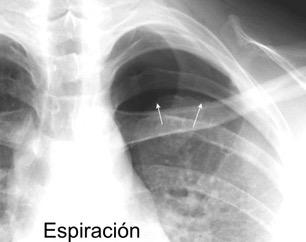

91. NEUMOTÓRAX EN ESPIRACIÓN

M. Bradley et al. Value of routine expiratory chest films in the diagnosis of pneumothorax.Arch Emerg Med.1991, F. Schramel, et al. Expiratory chest radiographs do not improve visibility of small apical pneumothoraces by enhanced contrast.Eur Respir J. 1996,

Sospecha de neumotórax Neumotórax